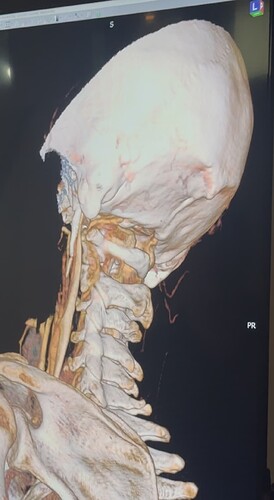

I have a cbct and CVA made wich shows elongated styloids and calcified stylohoids around 5 cm. Space left in neutral position between c1 is 3.5mm. Left IJV compression in laying position but there seems to be mainly some soft tissue compression there. So not due to compression of c1/styloid. The right is my dominant IJV.

Hi Rob & welcome! Looking at your CT, & obviously we’re not experts, I would estimate that your styloid & calcified ligament section is longer than 5 cm; on your left in the middle image it goes way past your C2 vertebra! We have found that the measurements from CTs are often wrong as it can be quite hard to measure accurately due to CT imaging being done in slices…

The IJVs do collapse naturally when flat, so it could be due to that, in your 3rd image it looks like the IJV is flattened higher up, so what would be right by the skull base. It could be like that naturally because of being flat for the CT, or it could be that it is being compressed where it emerges from the skull at the jugular foramen - if styloids are quite thick that is possible, & yours do look a little wide at the top… It looks like there could be something pinching the IJV between it & the styloid where you’ve marked too; we’ve had members who’ve had compression from an enlarged SCM muscle, the digastric muscle, omahyoid muscle, as well as other blood vessels & nerves… I’d guess where the compression is that the digastric muscle would be the most likely if it was a muscle, or maybe the stylohyoid muscle, although we don’t hear much about that one!

@Rob12345 - Welcome to our forum! I have nothing to add to what @Jules said, but did want to say WOW! You do have very long styloids. The “kink” in your ICA (internal carotid) isn’t really a kink more of a curve, but I can see based on the image, that it could be causing some slowed or backed up blood flow going into your brain. The IJV compression is curious as it appears to be more than the styloid causing the problem but clearly C1 seems not to be involved. I think Jules has made some logical assumptions regarding other possible compression culprits.

@Rob12345 - I can see you have bilateral IJV compression in the images you’ve posted & it’s possible the middle image in your first set of pictures is pointing to collateral veins. I’m not great at identifying collaterals, but I can say for sure your IJVs are being squashed between your styloids & C1.